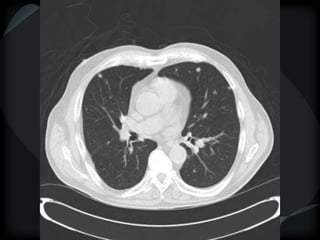

METS

random